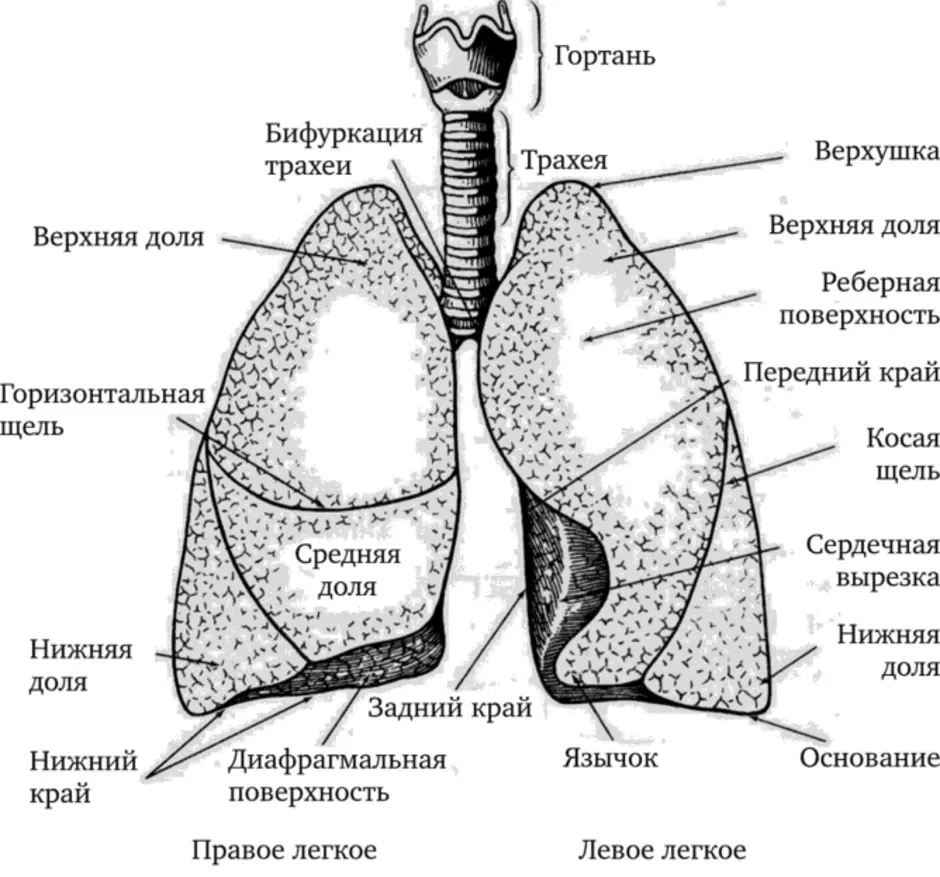

Роль легких в метаболических процессах